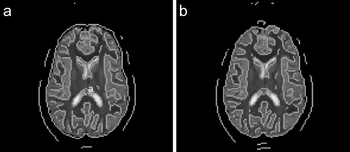

| A Variational Image-Based Approach to the Correction of Susceptibility Artifacts in the Alignment of Diffusion Weighted and Structural MRI. Read more... | ||